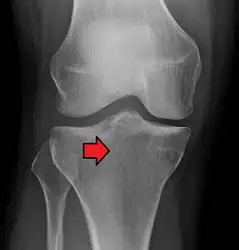

Subtle tibial plateau fracture on an AP X ray of the knee -